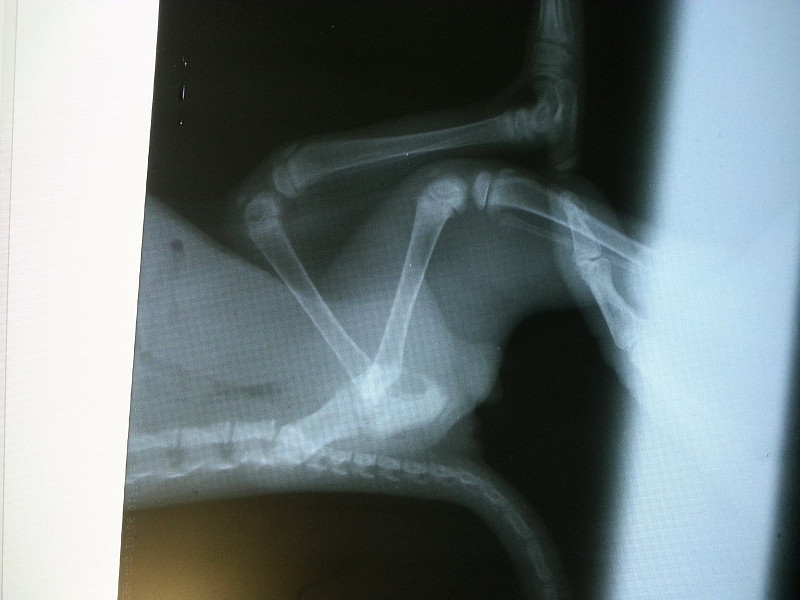

Перелом бедра у собаки

Перелом бедра у собаки 113 фотографий